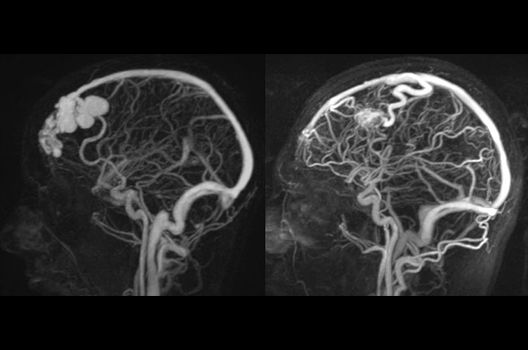

Die Magnetresonanztomographie (MRT) ist ein Verfahren, bei dem durch magnetische Kräfte Bilder des Körperinneren angefertigt werden. In der Neuroradiologie können manchmal kleinste Veränderungen schwere Folgen haben; daher forschen wir an der Entwicklung hochauflösender MRT-Sequenzen, mit denen diese Prozesse und auch einzelne Nervenfaserbahnen sichtbar gemacht werden können. Darüber hinaus sind bei vielen Erkrankungen des Gehirns die Blutgefäße betroffen. Daher arbeiten wir an der Neu- und Weiterentwicklung von MRT-Sequenzen zur Darstellung der Blutgefäße und zur Blutflussanalyse (sog. „Angio-MRT“). Einen besonderen Forschungsschwerpunkt unserer Klinik stellen die MR-Protonenspektroskopie und die funktionelle MRT dar, mit denen die Analyse einzelner chemischer Substanzen im Hirngewebe oder die Darstellung ausgewählter Hirnfunktionen möglich ist.